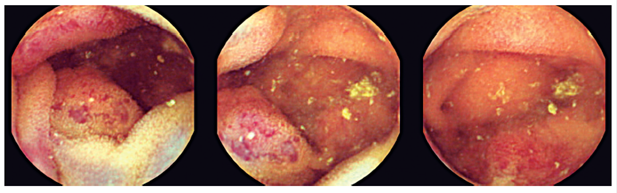

Subsequently, antegrade balloon enteroscopy was used to explore the middle jejunum. A discrete elevated, circular, hypervascularized lesion measuring approximately two cm between the proximal and middle jejunum hindered progression of the enteroscope. It was marked with Chinese ink with the help of an endoscopic needle above and below the lesion (Figures 2 and 3).

The macroscopic pathology description (Figures 4,5 and 6) revealed a segment of the small intestine that measured 11.5 cm long and was up to 3.5 cm in diameter and whose corresponding mesentery was without orientation. The mucosa was everted, and both ends were open. The serosa was smooth and marked with Chinese ink in the middle third. The mucosa showed a lesion in the form of a plaque with flattened violaceous folds. It measured 2.4 x 2.2 cm and contained cut microcysts filled with blood. The lesion was located 4 cm from the nearest edge and 5.2 cm from the opposite edge. The folds of rest of the intestinal mucosa appeared to be normal, and no other lesions were found. The serosa ink markings coincided with the submucosal lesion. The mesentery showed areas of congestion, but no lymph nodes were found. The microscopic slides of the wall of the small intestine (Figures 7,8,9 and 10) showed atypia with a proliferative lesion formed by large cavernous vascular channels with thin fibromuscular walls covered by the endothelium and filled with blood. This lesion was located primarily in the submucosa but extended focally to the lamina propria and to the internal muscle. The diagnosis was compatible with cavernous hemangioma.